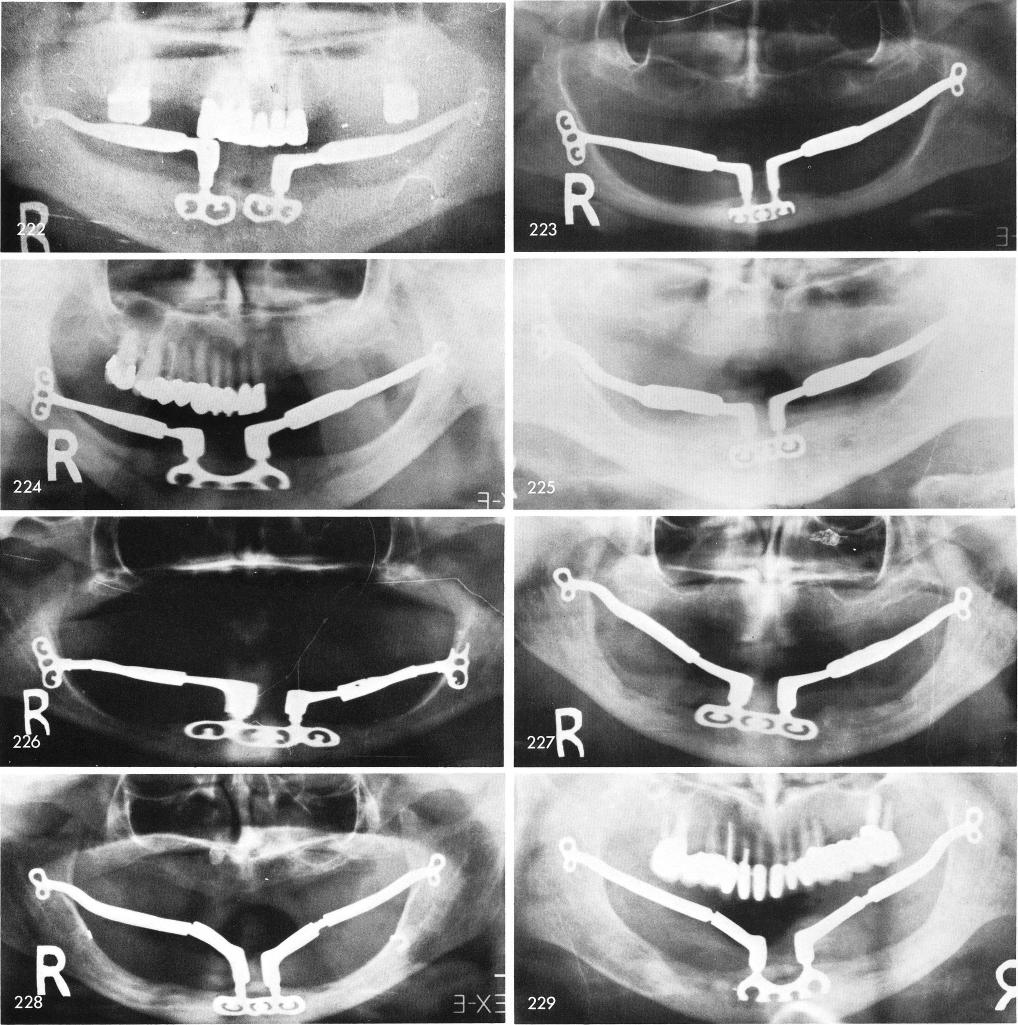

Mandibular Implants (published 1977)   Dr. Leonard I. Linkow